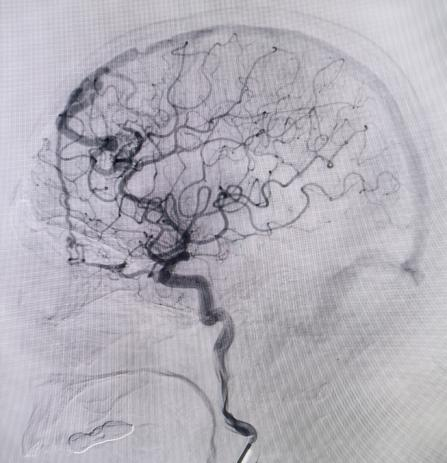

硬脑膜动静脉瘘患者同样在个性化方案中重获新生。患者因反复头晕,在外院怀疑静脉畸形,来到东方总院后,脑血管造影明确为硬脑膜动静脉瘘。通过详细的沟通,家属选择介入栓塞,吴全主任团队采用介入打胶栓塞的治疗方式,精准地堵住异常血管,一次性完全栓塞,术后患者头晕症状消失,生活质量大幅提升。

对于非责任动脉瘤的处理,医生们更是展现出专业与耐心。9个月前,患者动脉瘤破裂出血,当时造影发现2处动脉瘤,术中优先处理责任动脉瘤,待患者身体恢复后择期处理非责任动脉瘤。此次处理非责任动脉瘤,手术中造影,发现责任动脉瘤栓塞术后复发(3月前复查尚无),医生们当机立断,同期处理两个动脉瘤,省钱的同时,也成功为患者解除隐患。